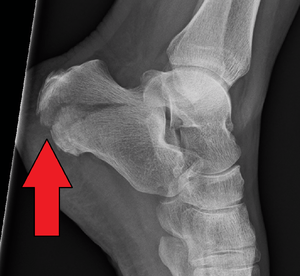

X-ray of a fractured calcaneus. | |

| eMedicine | radio/123 |

Calcaneal fracture is a fracture of the calcaneus. It is usually caused by a fall from height when one lands on their feet. These fractures represent approximately 2% of all fractures but 60% of tarsal bone fractures.[1] The name lover's fracture is derived from the fact that a lover may jump from great heights while trying to escape from the lover's spouse.[2]